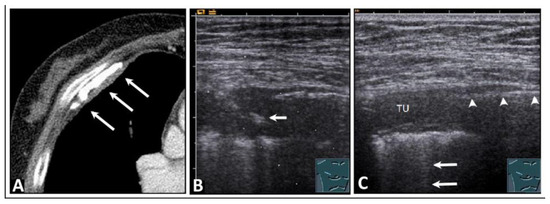

7. Other Pathologic Situations